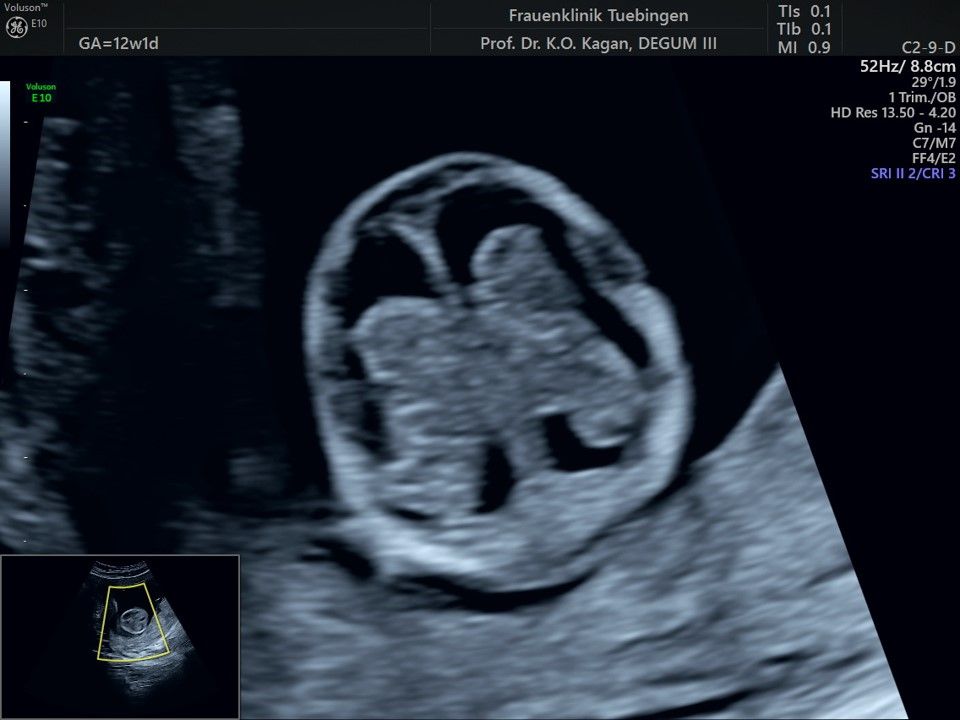

Herz